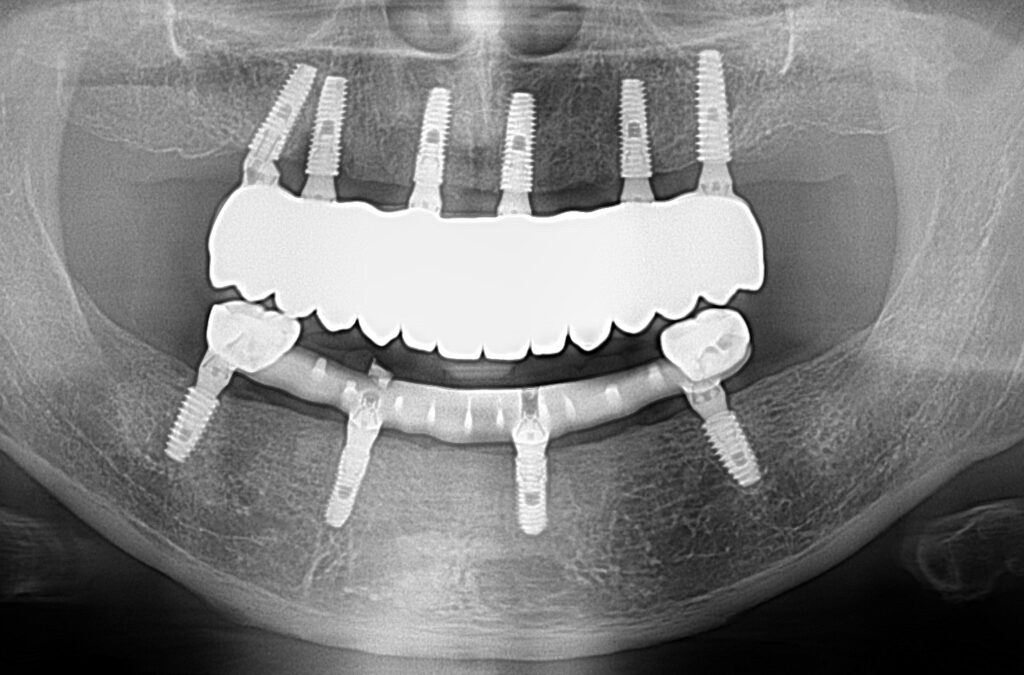

A selection of full arch fixed implant bridge patients after 5 years of wear